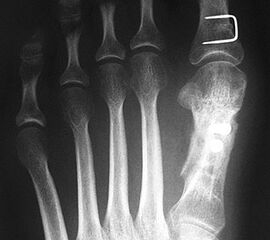

2) Rezidiv bei insuffizienter operativer Technik:

Die dorsoplantaren Röntgenaufnahmen zeigen eine Open-wedge Technik mit der normalerweise ein erhöhter intermetatarsaler Winkel gut zu korrigieren ist (Abbildung 3). Die Wirksamkeit einer Basisosteotomie ist umso größer, je proximaler diese durchgeführt wird. Je weiter distal die Osteotomie, umso geringer die Korrektur. Auf den postoperativen Bildern ist der distal unverändert große Abstand zwischen Metatarsale I und Metatarsale II erkennbar, bei gleichzeitiger Subluxation des Großzehengrundgelenks und dezentrierten Sesambeinen. Darüber hinaus finden sich initiale degenerative Veränderungen im Großzehengrundgelenk. Klinisch bestand eine hohe Weichteilspannung, bei verkürzter Extensor- und Flexor hallucis longus Sehne.  Daher wurde ein verkürzendes Verfahren zur Revision gewählt (Abbildung 4). Die Lapidusarthrodese stellt ein sehr zuverlässiges Verfahren zur Behandlung von Hallux valgus Rezidiven dar 9. Die Fusion des Tarsometatarsale-I-Gelenks kombiniert Stabilität mit einem hohen Korrekturpotenzial. Aufgrund der verfahrensimmanenten Verkürzung des ersten Strahls und der in diesem Fall bereits präoperativ vorhandenen Transfermetatarsalgie wurde die Entscheidung für eine verkürzte Weil-Osteotomie am zweiten bis fünften Strahl gefällt. Die Kombination beider Verfahren führte zu einem homogenen Metatarsale-Index und zu einer gleichmäßigen plantaren Druckverteilung 10. Die Hallux valgus interphalangeus Fehlstellung wurde mit einer Akin-Osteotomie korrigiert.